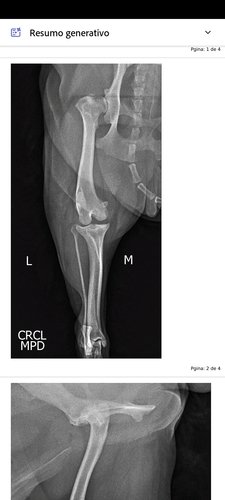

Infelizmente meu cachorro Pop rompeu o ligamento do joelho e precisa de uma cirurgia o mais rápido possível.